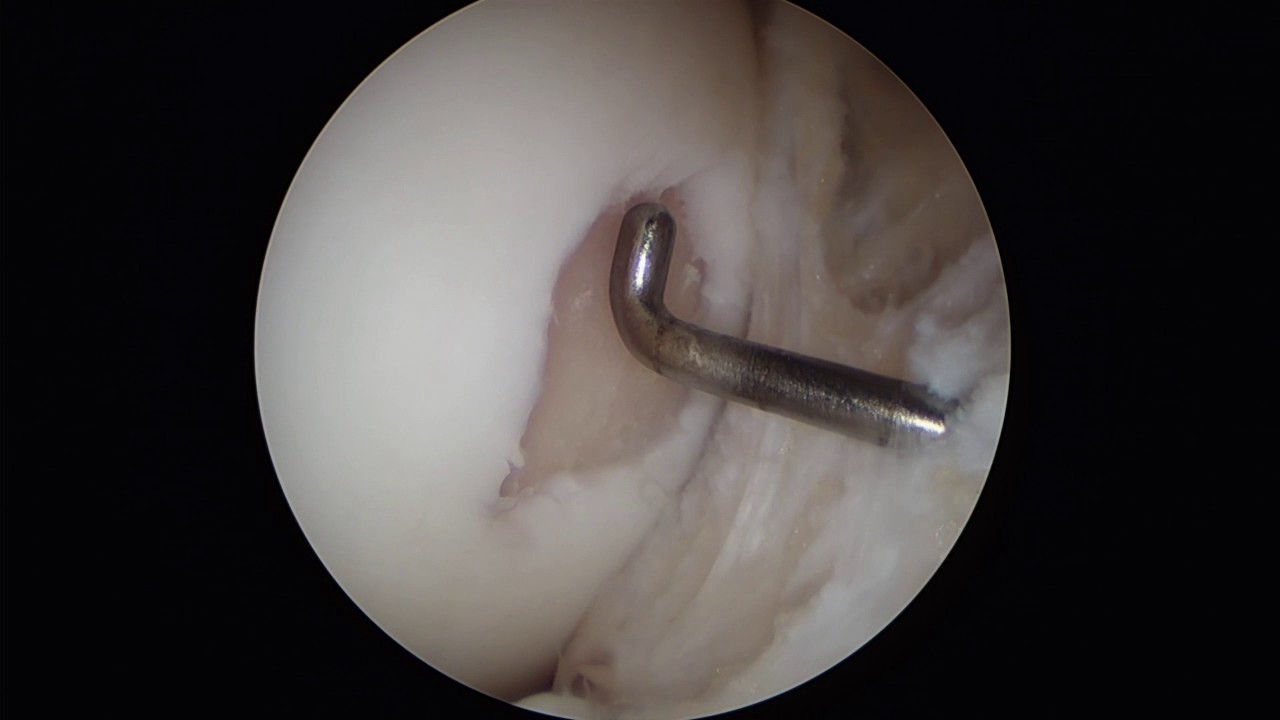

Dal 2005 Responsabile di Unita'​ Operativa di Endoscopia articolare presso la Casa di Cura Igea di Partinico ( Palermo ), con particolare dedizione alla chirurgia artroscopica di ginocchio.

Casistica personale : circa 10000 interventi di chirurgia artroscopica di ginocchio (trattamento di tutta la patologia meniscale, delle lesioni legamentose riguardanti il legamento crociato anteriore - posteriore e collaterali, della patologia sinoviale e delle lesioni cartilaginee con trapianti osteocondrali e tecniche utilizzanti cellule staminali in associazione con membrane semisintetiche tridimensionali di estere benzilico di acido ialuronico o con membrane biologiche di collagene porcino). Correzione delle deviazioni assiali degli arti con osteotomie correttive; correzione del malallineamento femoro rotuleo in artroscopia e artrotomia, chirurgia protesica.

Chirurgia di revisione del legamento crociato anteriore con studio TAC 3D e stampa 3D del ginocchio da operare.